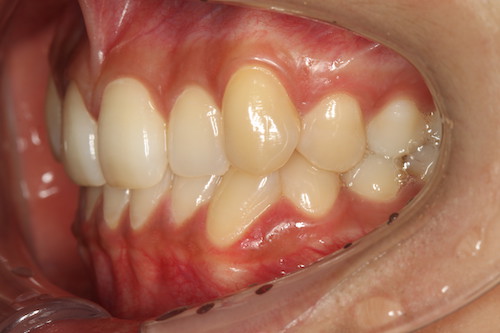

После